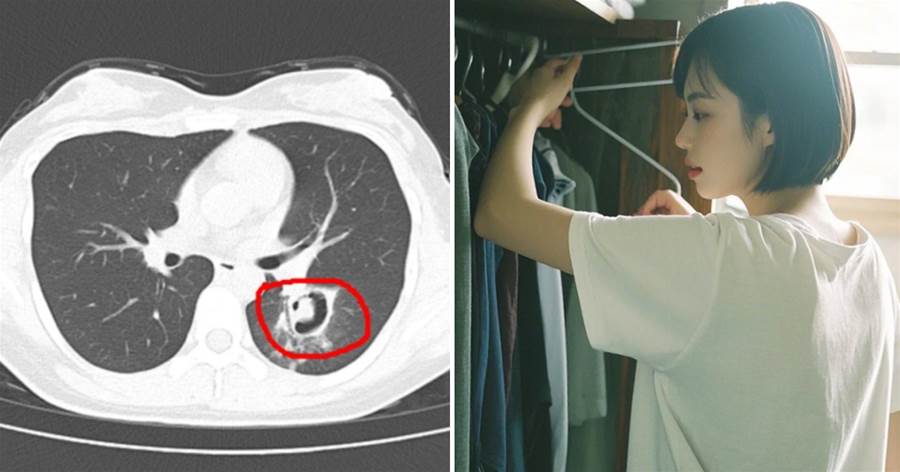

近日,一則「女子整理舊衣柜后高燒40℃」的新聞引發廣泛關注。據報道,該女子在整理家中久未開啟的舊衣柜后,出現持續高燒、劇烈咳嗽、全身乏力等癥狀,就醫檢查發現肺部竟「長滿」霉斑,被確診為霉菌性肺炎。這一案例為夏季居家健康敲響警鐘。

霉菌是一種常見的真菌,在溫暖潮濕的環境中極易滋生。該患者發病時正值梅雨季節,其家中衣柜長期未通風,為霉菌繁殖提供了理想環境。醫生解釋,當患者整理衣柜時,大量霉菌孢子隨灰塵揚起,通過呼吸道進入肺部,引發感染。

值得注意的是,該病初期癥狀與普通感冒相似,容易延誤治療。醫生特別提醒,若出現超過3天的高熱不退,或咳嗽伴隨胸痛等癥狀,應及時就醫檢查。